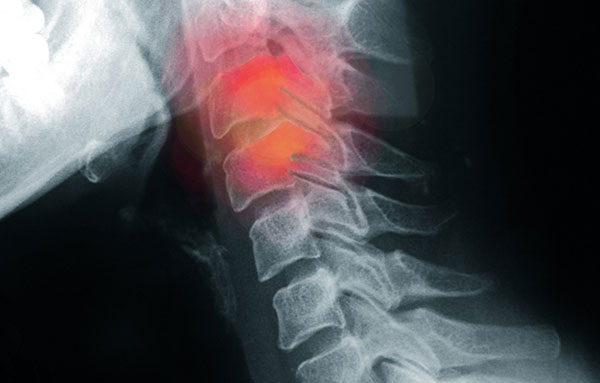

An x-ray (radiograph) is a quick, painless medical test that helps physicians diagnose and treat medical conditions. Radiography involves exposing a part of the body to a small dose of ionizing radiation to produce pictures of the inside of the body. X-rays are the oldest and most frequently used form of medical imaging. They are often used to help diagnose fractures in bones, or infection, injury or locating a foreign object in soft tissue. Diļ¬erent parts of the body absorb the x-rays in varying degrees. Dense bone absorbs much of the radiation while soft tissue, such as muscle, fat and organs, allow more of the x-rays to pass through them. As a result, bones appear white on the x-ray, soft tissue shows up in shades of gray and air appears black.